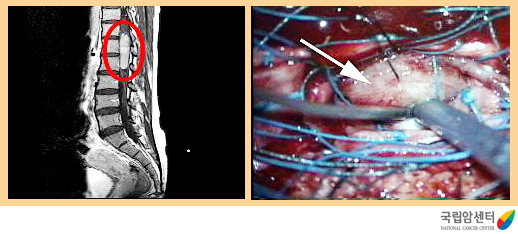

일차적 목적은 척수와 신경근의 기능을 회복하는 것입니다. 양성 비침윤성 종양 및 원발성 척수종양의 경우에는 근치를 목표로 하여 수술로 완전 제거하는 것이 최상의 치료방법이고, 악성종양이나 침윤성 종양의 경우에는 일시적인 신경 증상의 호전 또는 증상의 악화를 방지하는데 목표를 두어야 합니다. 수술 현미경과 초음파진단장비 등의 미세 신경 수술기법과 각각의 신경이 지배하는 피부 영역에 전기 신호를 감지 할 수 있는 전기생리학적 감시장치를 이용하면 척수내에 발생된 종양이라도 종양이 침범한 신경을 보호할 수 있어 신경학적 후유증 없이 완전 제거가 가능한 경우가 많습니다.

전이성 척추종양처럼 악성종양의 경우 척추체를 파괴하여 척추골절이 발생하기도 하므로 이런 경우는 기구를 이용한 척추 고정술이 필요하기도 합니다.

[ 척수종양의 자기공명영상촬영(MRI) 및 척수종양 수술 장면 ]